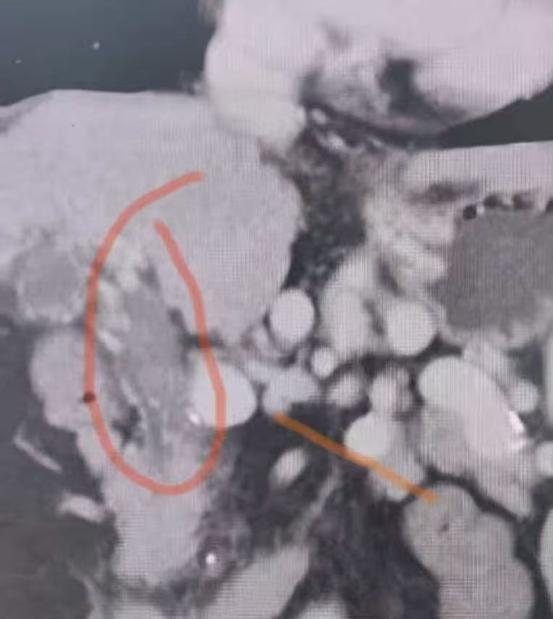

该患者为女性,因肝硬化合并食管胃底静脉曲张破裂出血多次入院,同时伴有严重血小板减少和大量腹水,身体状况极差,无法耐受传统外科手术。面对棘手的病情,任东铭主任团队详细评估病情,通过上腹部增强CT,团队精准掌握了患者的血管解剖结构。检查发现,患者的门静脉主干已完全闭塞,周围被大量迂曲、杂乱的侧支血管替代,呈现典型的“门静脉海绵样变性”——这是TIPS手术中公认的高难度挑战,穿刺难度极大,术中风险极高。

△术前